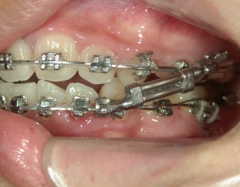

矯正歯科 治療途中 下顎の後退を改善する為、ツインフォースで下顎を前に出す

no.18_2196_治療中_右.jpgno.18_2196_治療中_正面.jpgno.18_2196_治療中_左.jpg